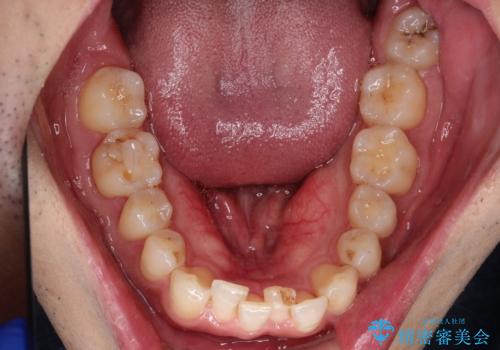

初診時の歯並びの状態としては、下顎に中等度のがたつき(叢生)がある状態でした。

抜歯は行わず下顎の奥のスペースを利用して歯をスライドする方法の他に親知らずの抜歯そして上下ともに歯列弓の拡大やディスキング(歯と歯の間の隙間を作る処置)を行い叢生を改善しました。

歯の大きさの不揃いが原因の正中のズレは、ディスキング量を調整することで合わせました。